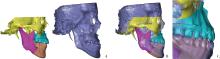

Figure 5

Evaluation of soft tissue (A) and hard tissue (B) symmetry"